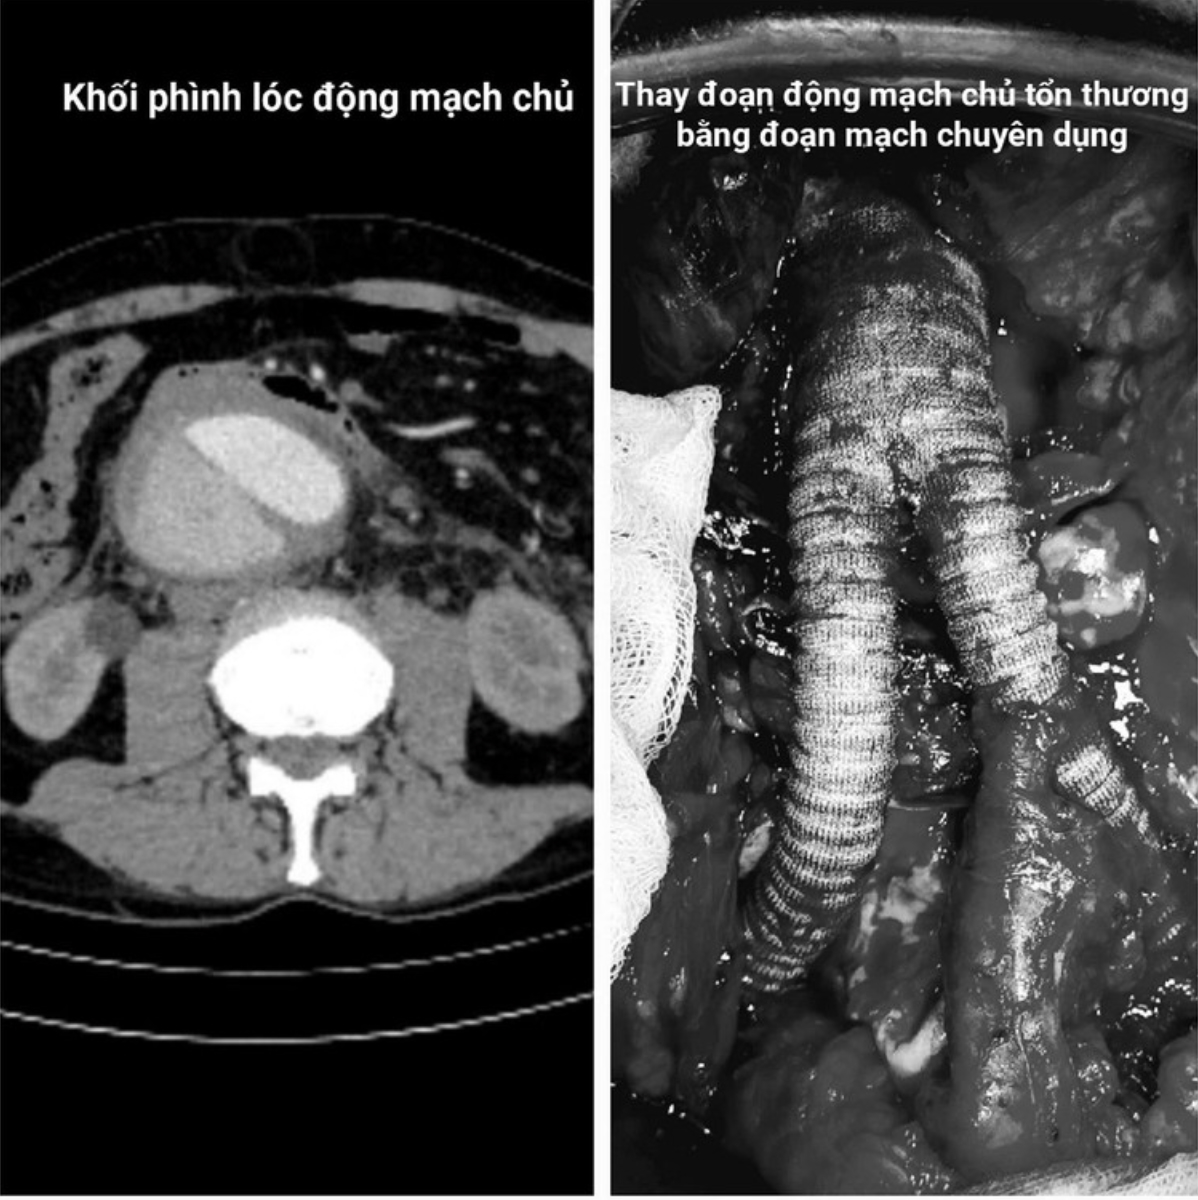

Ông Janusz (69 tuổi, du khách Ba Lan), đang du lịch tại Việt Nam thì đột ngột đau dữ dội vùng ngực lan xuống bụng. Sau khi được chẩn đoán “lóc tách động mạch chủ ngực - bụng Stanford B” tại một bệnh viện quốc tế, ông được chuyển đến Bệnh viện Bạch Mai.

Tại đây, các bác sĩ phát hiện thêm khối phình động mạch chủ bụng khổng lồ, đường kính 9cm, đang có dấu hiệu vỡ. Tình trạng này được ví như “quả bom nổ chậm”, đe dọa tính mạng từng phút. Cuộc mổ cấp cứu với tiên lượng sinh tử được kích hoạt khẩn cấp với sự phối hợp từ các chuyên khoa: mạch máu, gây mê, hồi sức, huyết học.

Khi mở ổ bụng, khối phình đã vỡ và máu tràn vào khoang sau phúc mạc. Ê-kíp đã kiểm soát điểm vỡ, bảo tồn các nhánh mạch máu sống còn, thay đoạn động mạch tổn thương bằng ống ghép nhân tạo. Từng mũi khâu được thực hiện dưới kính vi phẫu, keo sinh học cũng được sử dụng để tăng cường kiểm soát chảy máu. Suốt quá trình mổ, huyết áp bệnh nhân được duy trì ổn định nhờ sự phối hợp chặt chẽ của ê-kíp gây mê.